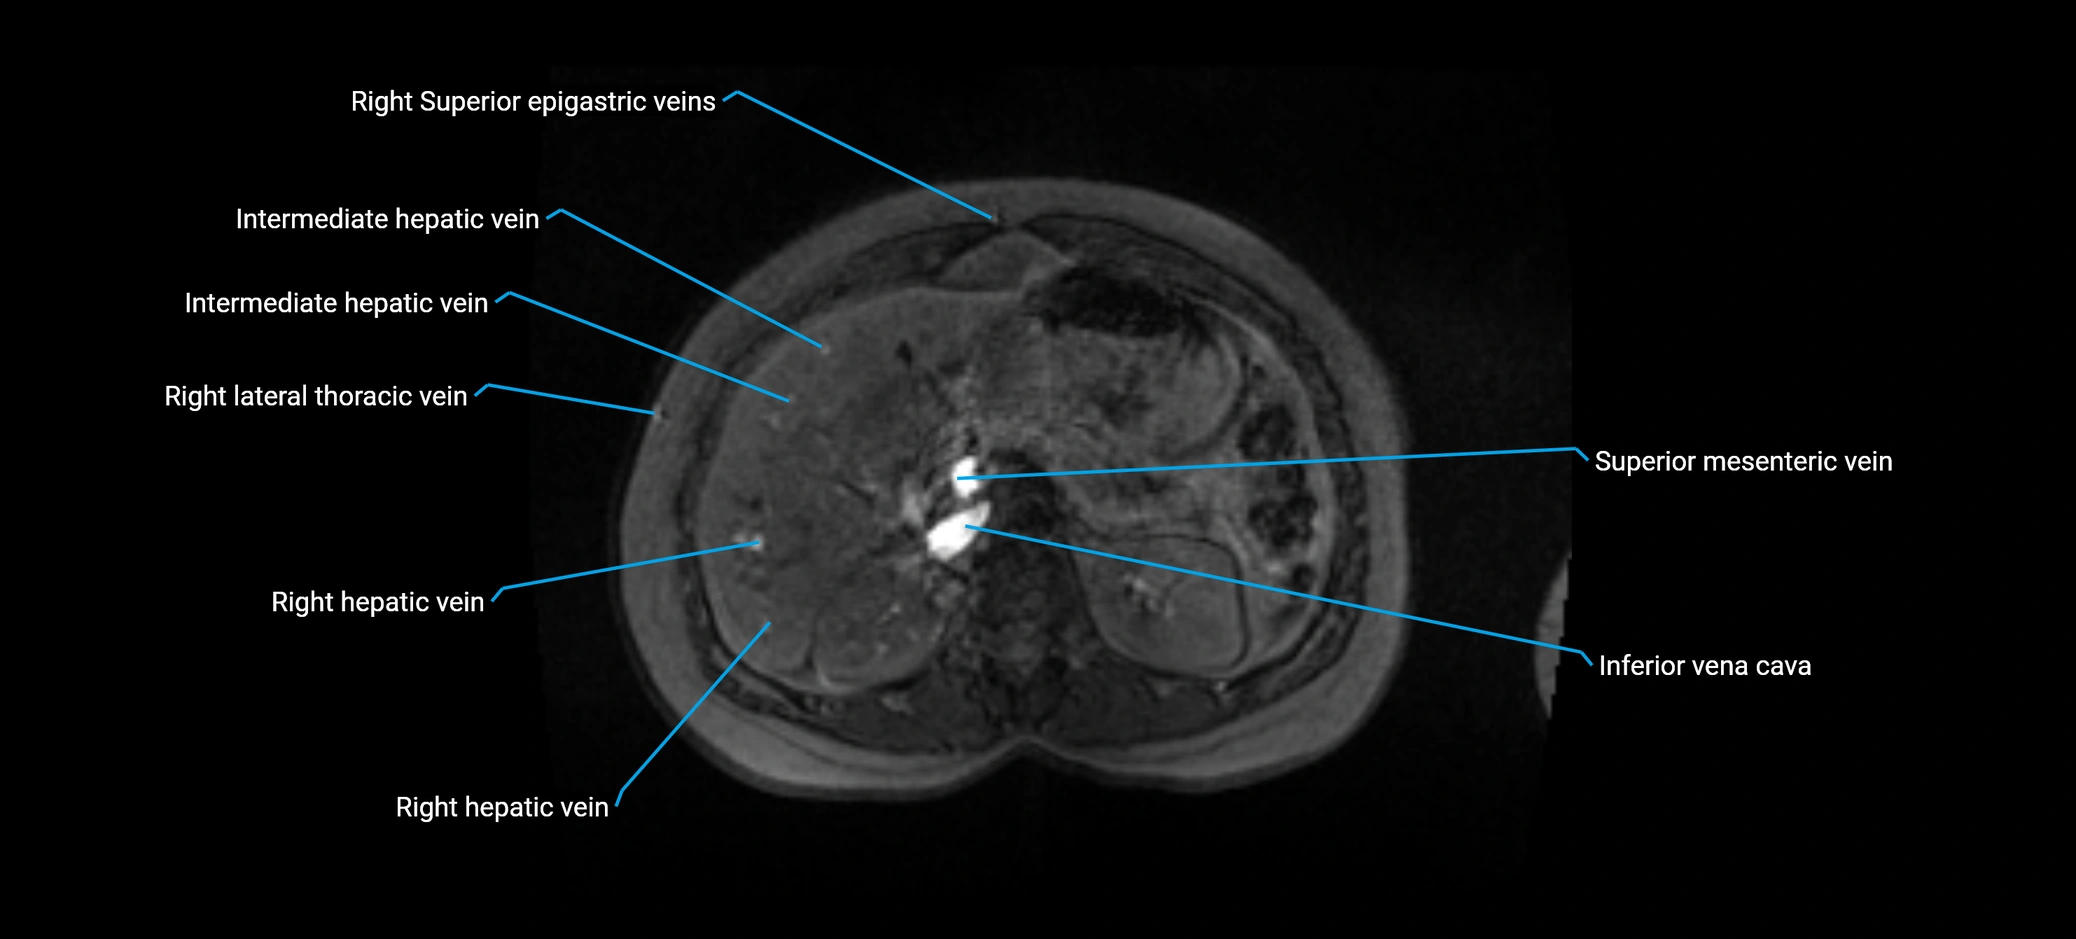

MRI image

image